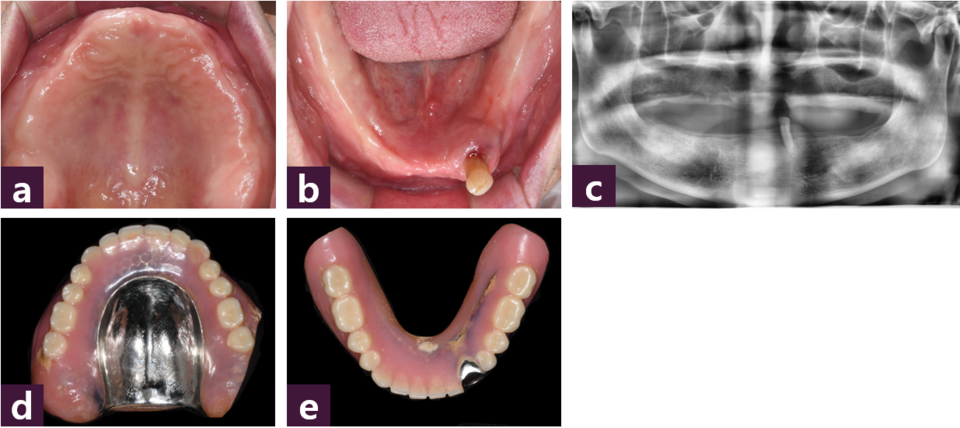

본 증례는 70세 남성환자로 상악 총의치와 하악 좌측 견치를 지대치로 하는 국소의치를 장착하고 있던 중 [그림 1],

치주질환으로 하악 좌측 견치의 발치가 요구되는 상황에서 임플란트 식립을 통해 고정성 보철을 하고 싶다는 주소로 내원하였다.

환자의 특이한 전신질환은 없었고 전반적인 치조골 상태는 양호하였다.

치료계획으로 의치에 대한 환자의 거부감과 양호한 치조골 상태를 고려하여 상악에는 10개, 하악에는 8개의 MagiCore 임플란트를 식립하여 치료하는 임플란트 지지 고정성 보철을 선택하였다.